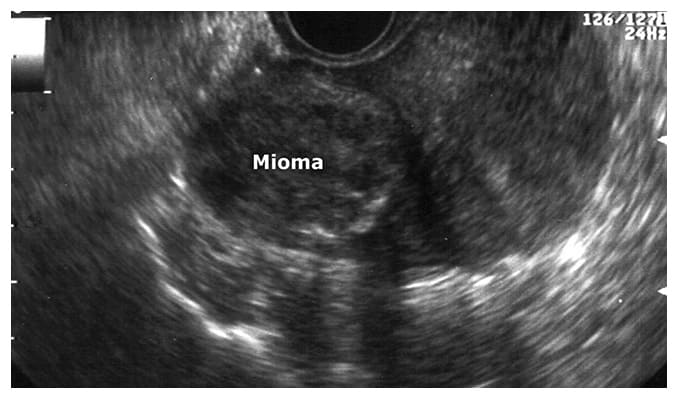

Una de las principales herramientas con las que contamos los ginecologos hoy en dia para detectar los miomas, además del historial de hemorragia menstrual y de dolor, que algunas pacientes pueden presentar, esta el ultrasonido que de rutina se realiza en el consultorio, ya que muchas veces los miomas son asintomáticos.

También se pueden usar estudios como la tomografía o la resonancia sin embargo el ultrasonido tiene una efectividad diagnostica en médicos con experiencia cerca del 100%.